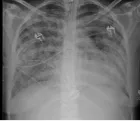

Figure 2:

The posterior plate is broken in one big fragment. 90 days after it is anatomically in place.